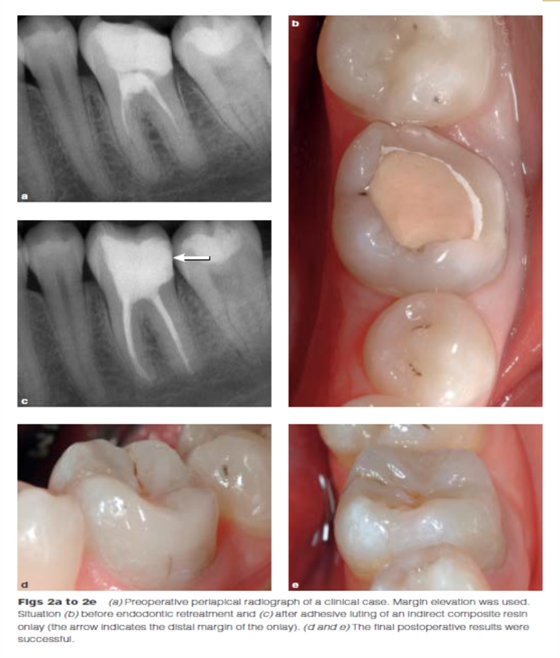

DME是用一個改良彎曲的成型片接堆放復合樹脂來提升齦壁高度,使其能夠在修復過程中使用橡皮障封閉邊緣,可以在固化前適當?shù)囊瞥嘤嗟膹秃蠘渲?。DME應(yīng)該在即刻牙本質(zhì)封閉(IDS)之后,在使用橡皮障的條件下,且僅在邊緣可被改良的成型片適當隔離時直接獲得。否則,這個技術(shù)不能使用。在最終取印前,需要拍攝咬合翼片來評估復合樹脂在齦邊緣區(qū)域的密合度(有無懸突或缺陷)。同樣需要仔細隨訪來評估軟組織的健康和是否需要外科手術(shù)干預。只要可能,在牙髓治療前就應(yīng)通過DME術(shù)制造假壁,使根管治療更完善(圖2、3)。圖4展示了一個典型DME術(shù)的適應(yīng)癥。

Dietschi和Spreafico在1998年提出了另一種方法,即在間接修復體的下面放置一個復合樹脂基底來取代冠向提升邊緣(圖1)。這個方法即我們所知的齦壁提升術(shù)(DMG)是在橡皮障隔離下完成的?(This procedure,…,is performed under rubber dam isolation following the placement of a matrix.)如今,DME(齦壁提升術(shù))通常與IDS(即刻牙本質(zhì)封閉術(shù))聯(lián)合使用來促進間接粘接修復體的粘接和齦邊緣的封閉。此外,邊緣的齦上提升,粘接復合樹脂基底被用于封閉牙本質(zhì)、加強潛在牙尖?(reinforce undermined cusps),充填倒凹(fill undercuts),以及為嵌體/高嵌體修復提供必要的幾何形態(tài)。